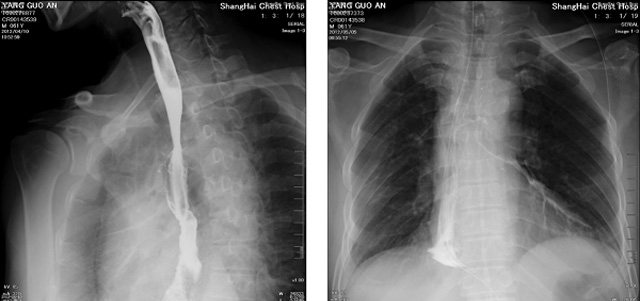

DR设备在2020年的新冠疫情中,加速了市场调整。以医院为主的向二三级市场转变。特别是小巧灵活的移动DR设计,填补CT和磁共振不能三维检查的缺点,满足内科外科特别是骨科的影像诊断需求?;褂行鮀R设备CT断层射线系统。使用锥束成像技术对整个脊柱和整个下肢进行了体积三维扫描。无需使用对比剂,即可使用X射线呼吸功能标测来模拟模拟气流和血流,以评估患者的肺动脉血栓。

数字化X线摄影依然是患者初筛的关键一环。静态DR限制于探测器平台。只能进行简单普通的数字化影像检查。胸部的疾病没办法筛查出微小的病灶。这样导致DR慢慢的被CT跟磁共振代替。这样造成了原来配套的数字化影像DR设备的 闲置。所以DR需要跟CT融合扩大DR的检查使用场景。为DR提高更多的市场价值。X射线技术的原始形式和面向未来的可能性打破了CT成像和DR成像扫描技术之间的限制。融合成像趋势更加明显,多峰成像趋势发展更加迅速。